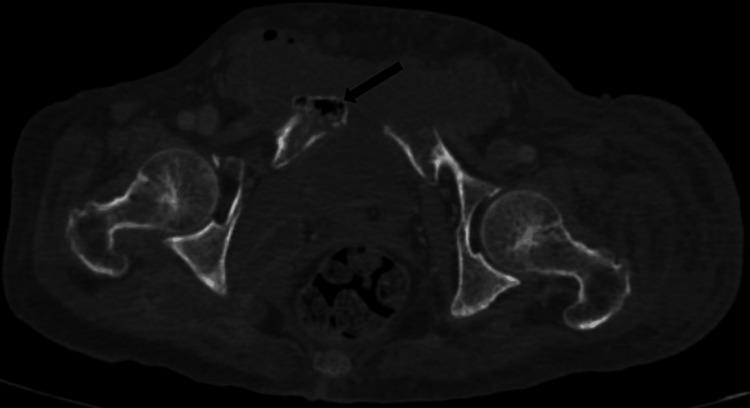

Emphysematous osteomyelitis is an uncommon and fatal disease that can only be confirmed with a contrast-enhanced CT scan showing characteristic features of air locules within the bone. It usually occurs in the setting of existing comorbidities and suppressed immune system resulting in widespread bacteremia which may be mono or poly-microbial. Presented here is a case of this disease caused by an unusual anaerobe affecting the pubic bone. This case emphasizes the importance of early imaging as it is crucial for the diagnosis and can facilitate early aggressive management. Moreover, it highlights the importance of early intravenous antibiotics and surgical intervention, which can be life-saving and result in a better outcome in the future.

气肿性骨髓炎是一种罕见的致命疾病,只有通过增强CT扫描显示骨内有特征性的小气腔才能确诊。它通常发生在存在合并症和免疫系统抑制的情况下,导致广泛的菌血症,可能是单一微生物或多种微生物感染。本文介绍了一例由一种不常见的厌氧菌引起的耻骨气肿性骨髓炎病例。该病例强调了早期影像学检查的重要性,因为它对诊断至关重要,并且有助于早期积极治疗。此外,它突出了早期静脉使用抗生素和手术干预的重要性,这可能挽救生命并在未来带来更好的结果。